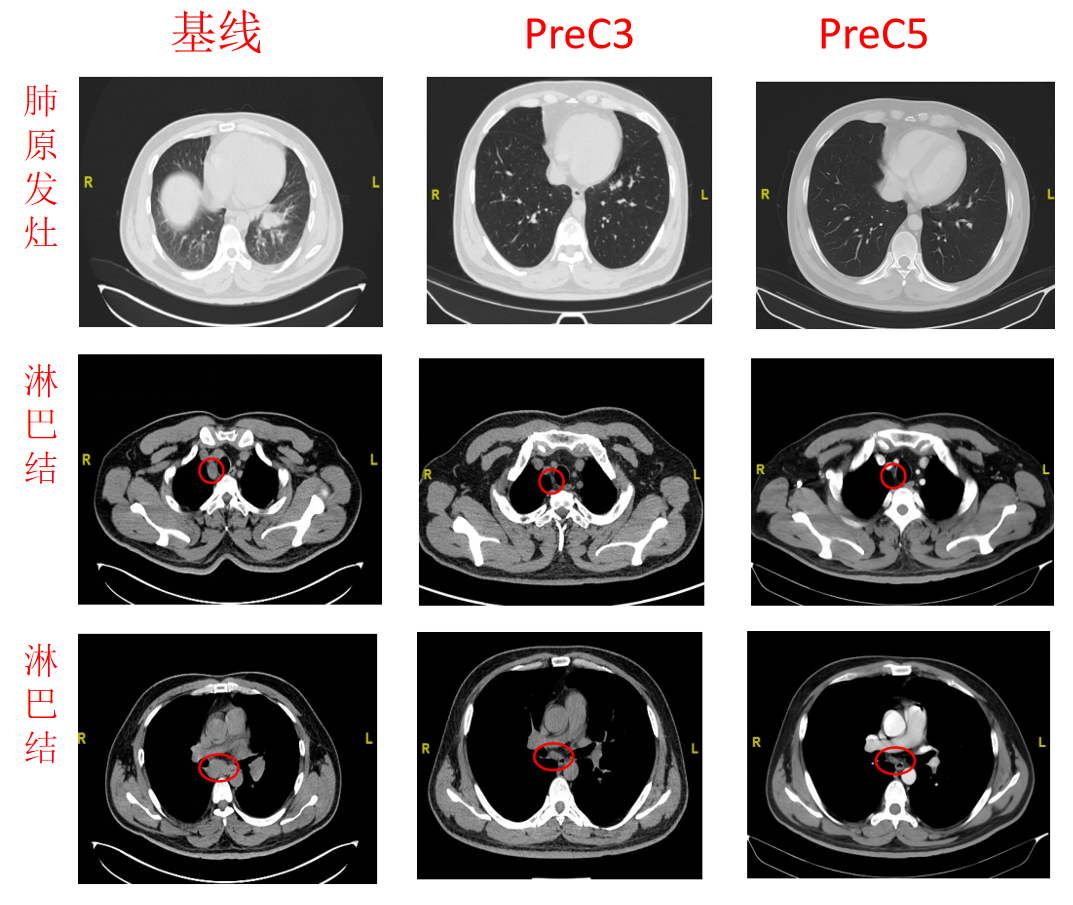

影像学检查:

PreC3:

CT(2022.7.5):左肺MT治疗后,左肺下叶近肺门软组织密实,牵拉临近胸膜。两侧胸廓对称,两肺纹理清晰,走向自然,余肺叶内未见明显异常密度阴影。纵膈稍大淋巴结。

MRI(2022.7.6):肝脏表面光滑,肝脏多发T1WI低信号、T2WI略高信号结节,较前稍缩小减少,大者约17mm,增强后呈轻度强化,肝胆排泄期强化退出,肝内外胆管无扩张。胸腰椎多发转移部分稍缩小。

PreC5:

CT(2022.8.22):左肺MT治疗后,左肺下叶近肺门软组织密实同前,牵拉临近胸膜。两侧胸廓对称,两肺纹理清晰,走向自然,另左肺下叶小结节,大者约4mm。纵膈未见明显淋巴结。肝内多发结节。

MRI(2022.8.19):肝脏表面光滑,肝脏多发T1WI低信号、T2WI略高信号结节,部分较前稍缩小,大者约15mm,增强后呈轻度强化,肝胆排泄期无明显摄取,肝内外胆管无扩张。胸腰椎多发异常信号灶,较前缩小。

图5.基线、C3、C4的胸、腹CT和MR影像